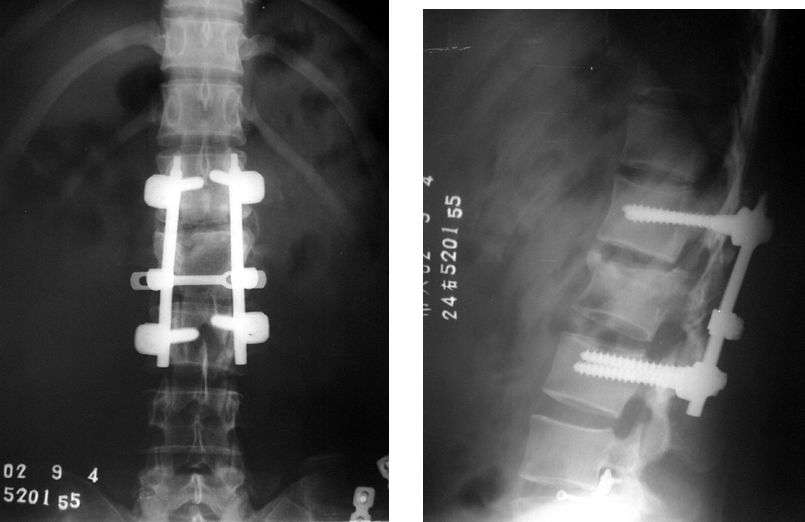

Если все тело стабильно, перелом со смещением следует оперировать немедленно при наличии неврологической симптоматики.

Для ЧМЕДИТЕХ, у нас есть очень полная линейка имплантатов для ортопедической хирургии и соответствующих инструментов, включая продукты имплантаты позвоночника, интрамедуллярные гвозди, травматическая пластина, Стопорная шайба, черепно-челюстно-лицевой, протез, электроинструменты, внешние фиксаторы, артроскопия, ветеринарная помощь и сопутствующие им наборы инструментов.